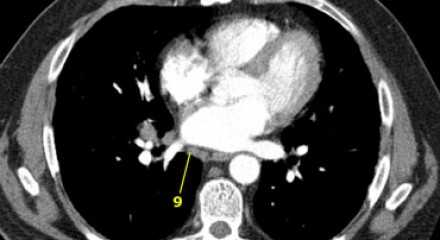

На постконтрастном изображении белой стрелкой указан увеличенный лимфатический узел IV группы. У пациента удалена правая доля щитовидной железы и правая яремная вена, что указано чёрной стрелкой, всвязи с папиллярной карциномой.